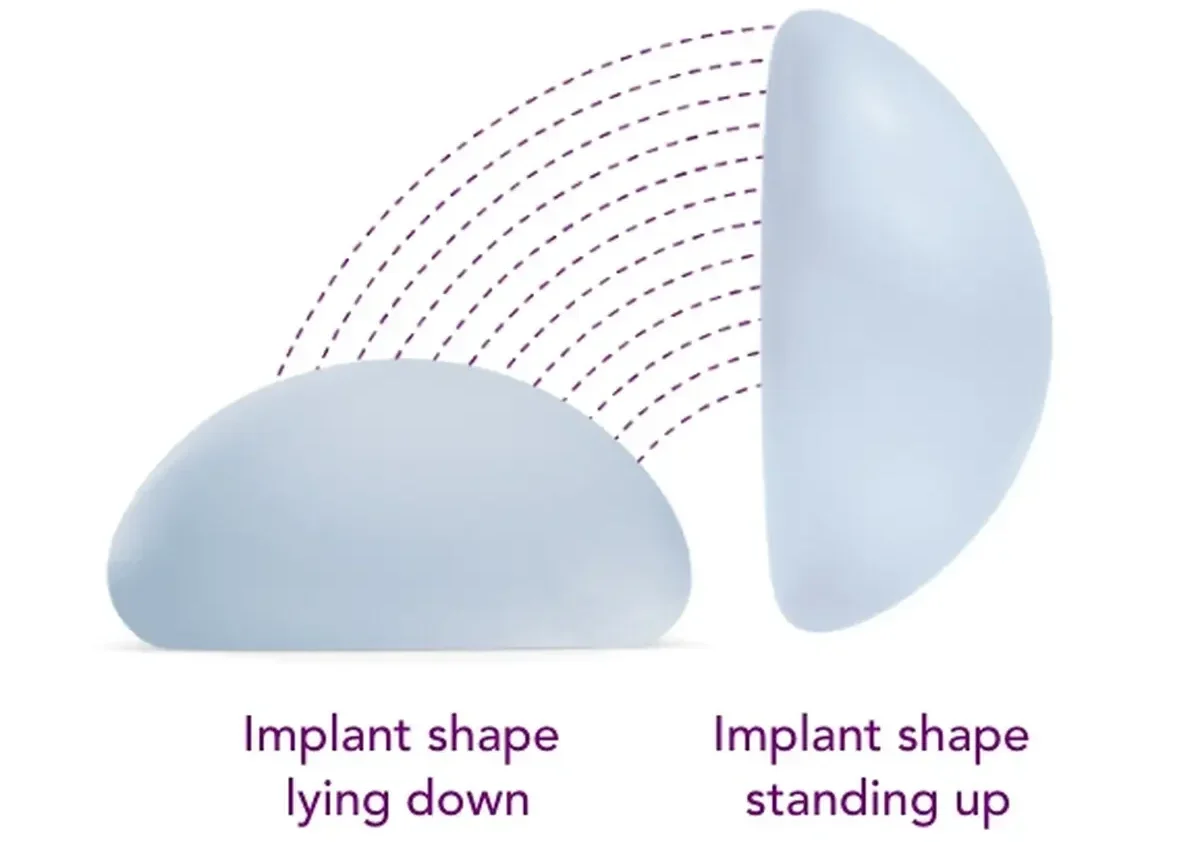

The implant choice should be based on your anatomy and goals, not on brand names alone. Different implants can create different levels of softness, fullness, projection, and movement.

Patients who prioritise a softer, more natural-looking breast movement and a less obviously augmented look.